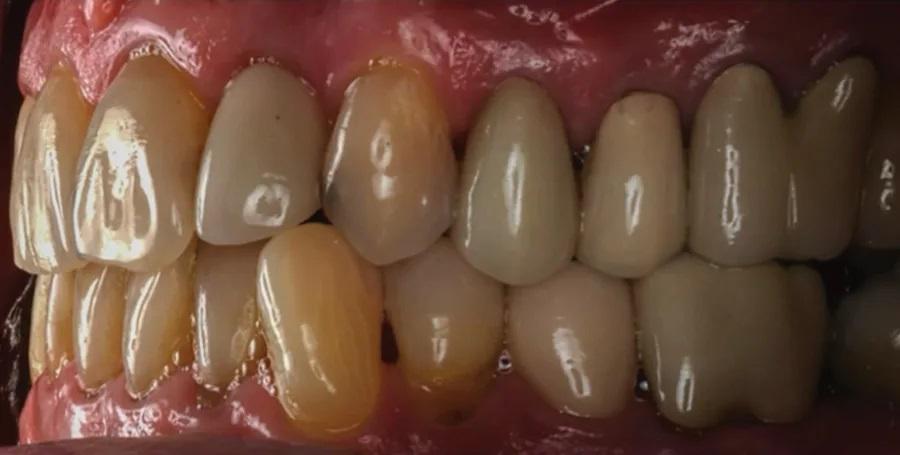

На контрольном осмотре через 16 месяцев клиническая оценка выявила сохраненный объем гребня и стабильную кератинизированную мягкую ткань (Фото 22 и Фото 23). Рентгенологический анализ подтвердил стабильный уровень кости вокруг имплантата № 2.4 и положительные рентгенологические изменения, свидетельствующие о регенерации тканей на медиальной поверхности зуба № 2.5, включая восстановление периодонтальной связки (Фото 24).

Фото 22 и Фото 23. На контрольном осмотре через 16 месяцев: интраоральный окклюзионный вид (Фото 22) и латеральный вестибулярный вид (Фото 23) демонстрируют реставрацию на имплантате с винтовой фиксацией.